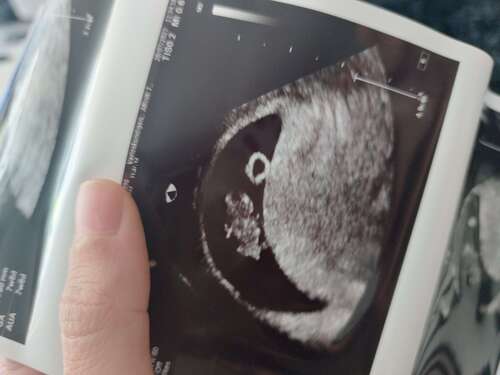

Wat lief dat je dat vraagt! Ik heb vanochtend mijn 1e echo gehad en een moo ...

Jeeeej wat een fijn nieuws! En mooi om al zo'n duidelijke echo te hebben mét een kloppend hartje! Geweldig. Geniet van dit nieuws!